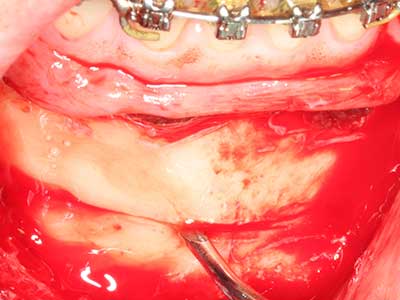

Autologous bone transplants are used in the form of blocks, shells, rings and are also combined with bone replacement materials as chips. If the implant site is prepared at the same time as the augmentation, various bone filter systems have proven effective for collecting the resulting bone chips. As an alternative, the implant site can be prepared using a low-speed device without irrigation. If an implant is not inserted, bone chips can be harvested from the periphery with bone scrapers. This is also possible with piezo surgery using specialized attachments that yield higher-quality bone chips compared chips harvested with round drills, as has been confirmed in a study comparing the two methods (Chiriac, Herten et al. 2005).

Piezo surgery has additional advantages when harvesting bone blocks. In addition to the high precision with osteotomy described above, the use of the thin saw tips specifically minimizes loss of material. Greater loss of material during harvesting can be expected with the thicker instrument tips, particularly when using Lindemann drills (Lakshmiganthan, Gokulanathan et al. 2012). The basal separation, which is necessary particularly for retromolar block transplants, is simplified by specially designed rectangular saws, with the result that piezo surgery is viewed as a precise, simple and safe procedure for harvesting retromolar bone blocks (Happe 2007) (Fig. 1-12).